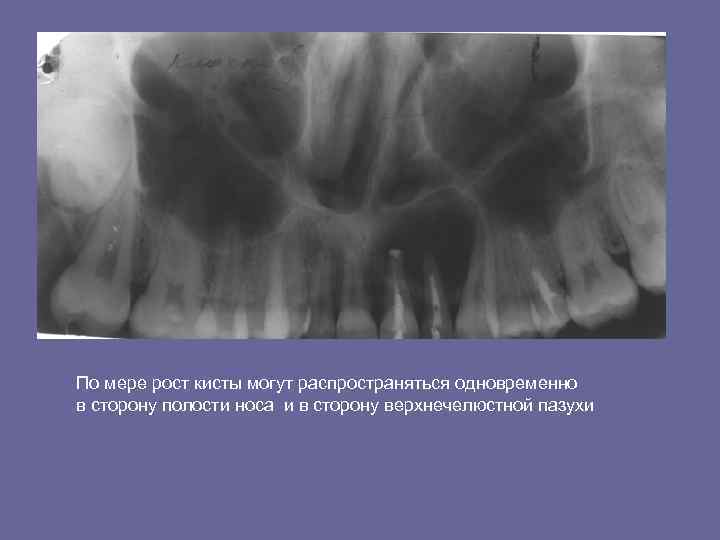

По мере рост кисты могут распространяться одновременно в сторону полости носа и в сторону верхнечелюстной пазухи